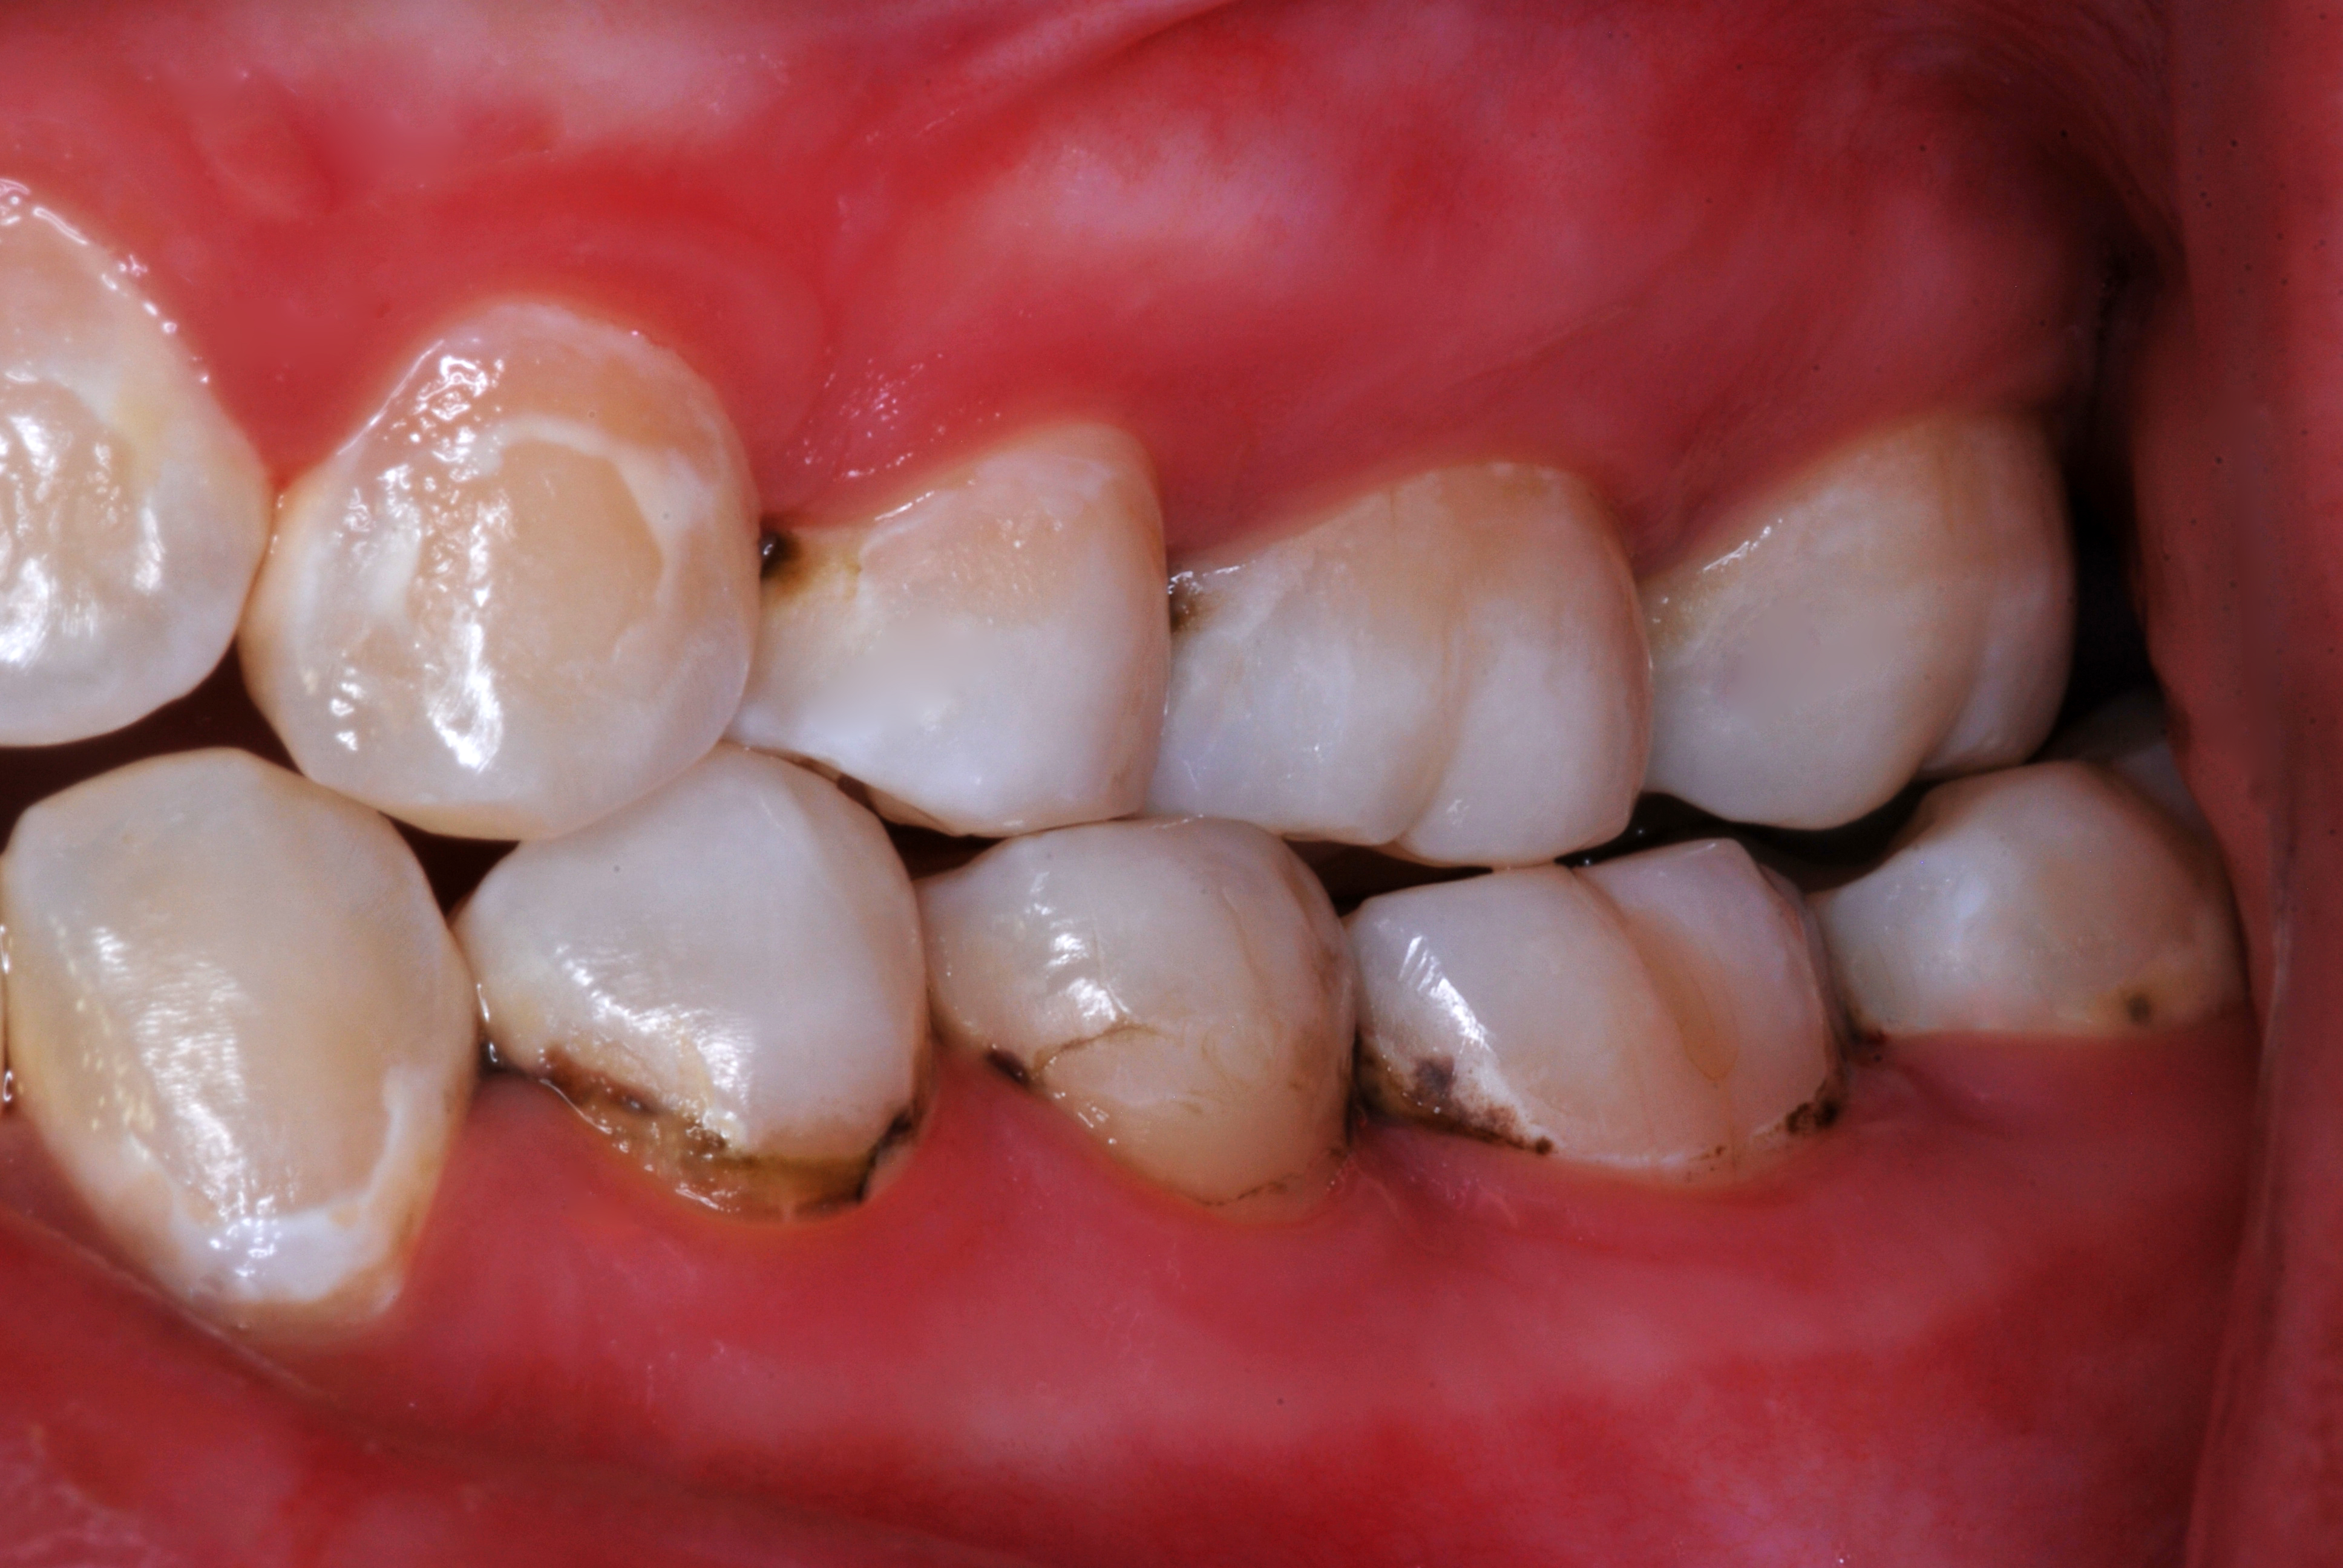

(2.) Lingual and facial maxillary views of 5-year-old patient, 1 year after caries attenuation with SDF. The parents were not concerned about the black staining.

Figure 2

(3.) Lingual and facial maxillary views of 5-year-old patient, 1 year after caries attenuation with SDF. The parents were not concerned about the black staining.

Figure 3